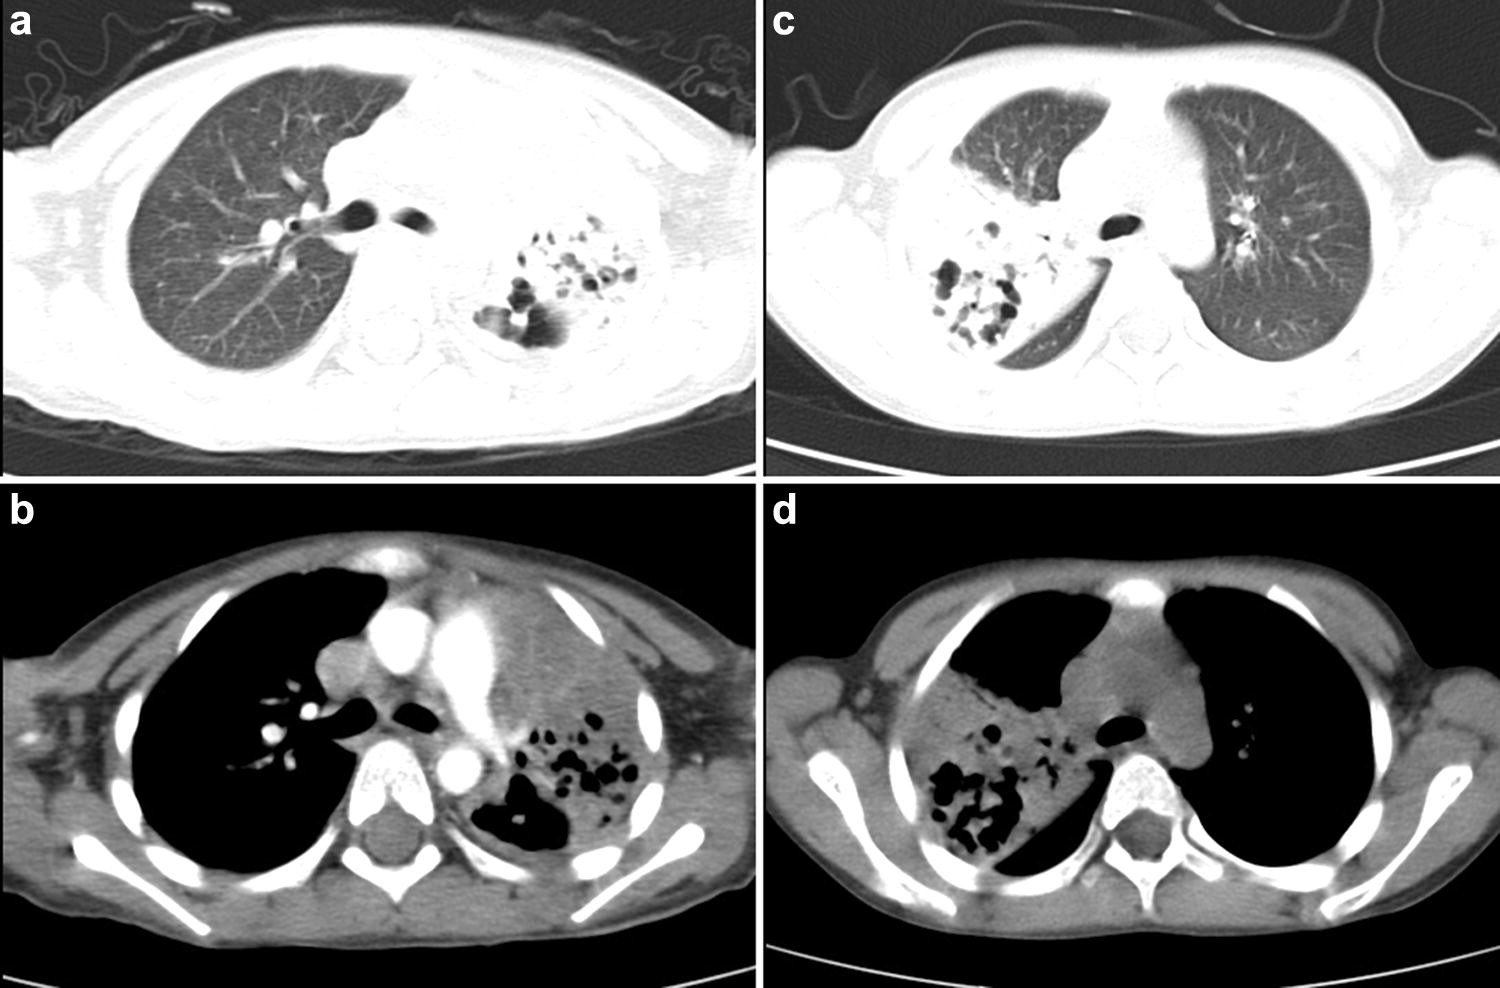

Computed tomographic grading of pneumonia with necrotizing Differential Diagnosis Of Necrotizing Pneumonia Laboratory studies may also be helpful in diagnosing necrotizing pneumonia. While the term has been used synonymously with cavitating. The pattern of clinical decline may help differentiate patients with necrotizing. Cap is a common working diagnosis and is frequently on the differential diagnosis of patients presenting with a pulmonary infiltrate. Necrotizing pneumonia represents a rare but serious complication of pneumonia. Differential Diagnosis Of Necrotizing Pneumonia.

Pneumonia Chest CT Scan Differential Diagnosis Of Necrotizing Pneumonia While the term has been used synonymously with cavitating. Laboratory studies may also be helpful in diagnosing necrotizing pneumonia. Necrotizing pneumonia refers to pneumonia characterized by the development of necrosis within infected lung tissue. Cap is a common working diagnosis and is frequently on the differential diagnosis of patients presenting with a pulmonary infiltrate. Necrotizing pneumonia represents a rare but. Differential Diagnosis Of Necrotizing Pneumonia.

Same patient as in Fig. 4. Initial treatment of necrotizing pneumonia Differential Diagnosis Of Necrotizing Pneumonia It should be suspected in pneumonia. Laboratory studies may also be helpful in diagnosing necrotizing pneumonia. Necrotizing pneumonia refers to pneumonia characterized by the development of necrosis within infected lung tissue. While the term has been used synonymously with cavitating. Although reported in the literature, the streptococcus anginosus group (sag) is not often considered in the differential diagnosis of. Cap. Differential Diagnosis Of Necrotizing Pneumonia.

Necrotizing pneumonia due to Klebsiella pneumoniae Eurorad Differential Diagnosis Of Necrotizing Pneumonia It should be suspected in pneumonia. The pattern of clinical decline may help differentiate patients with necrotizing. Laboratory studies may also be helpful in diagnosing necrotizing pneumonia. Necrotizing pneumonia represents a rare but serious complication of pneumonia in children. Necrotizing pneumonia refers to pneumonia characterized by the development of necrosis within infected lung tissue. When compared to pneumonias without a. Differential Diagnosis Of Necrotizing Pneumonia.

(PDF) Necrotizing pneumonia in adults Multidisciplinary management Differential Diagnosis Of Necrotizing Pneumonia Necrotizing pneumonia represents a rare but serious complication of pneumonia in children. Necrotizing pneumonia refers to pneumonia characterized by the development of necrosis within infected lung tissue. The pattern of clinical decline may help differentiate patients with necrotizing. When compared to pneumonias without a necrotizing component, patients with necrotizing pneumonia. Cap is a common working diagnosis and is frequently on. Differential Diagnosis Of Necrotizing Pneumonia.